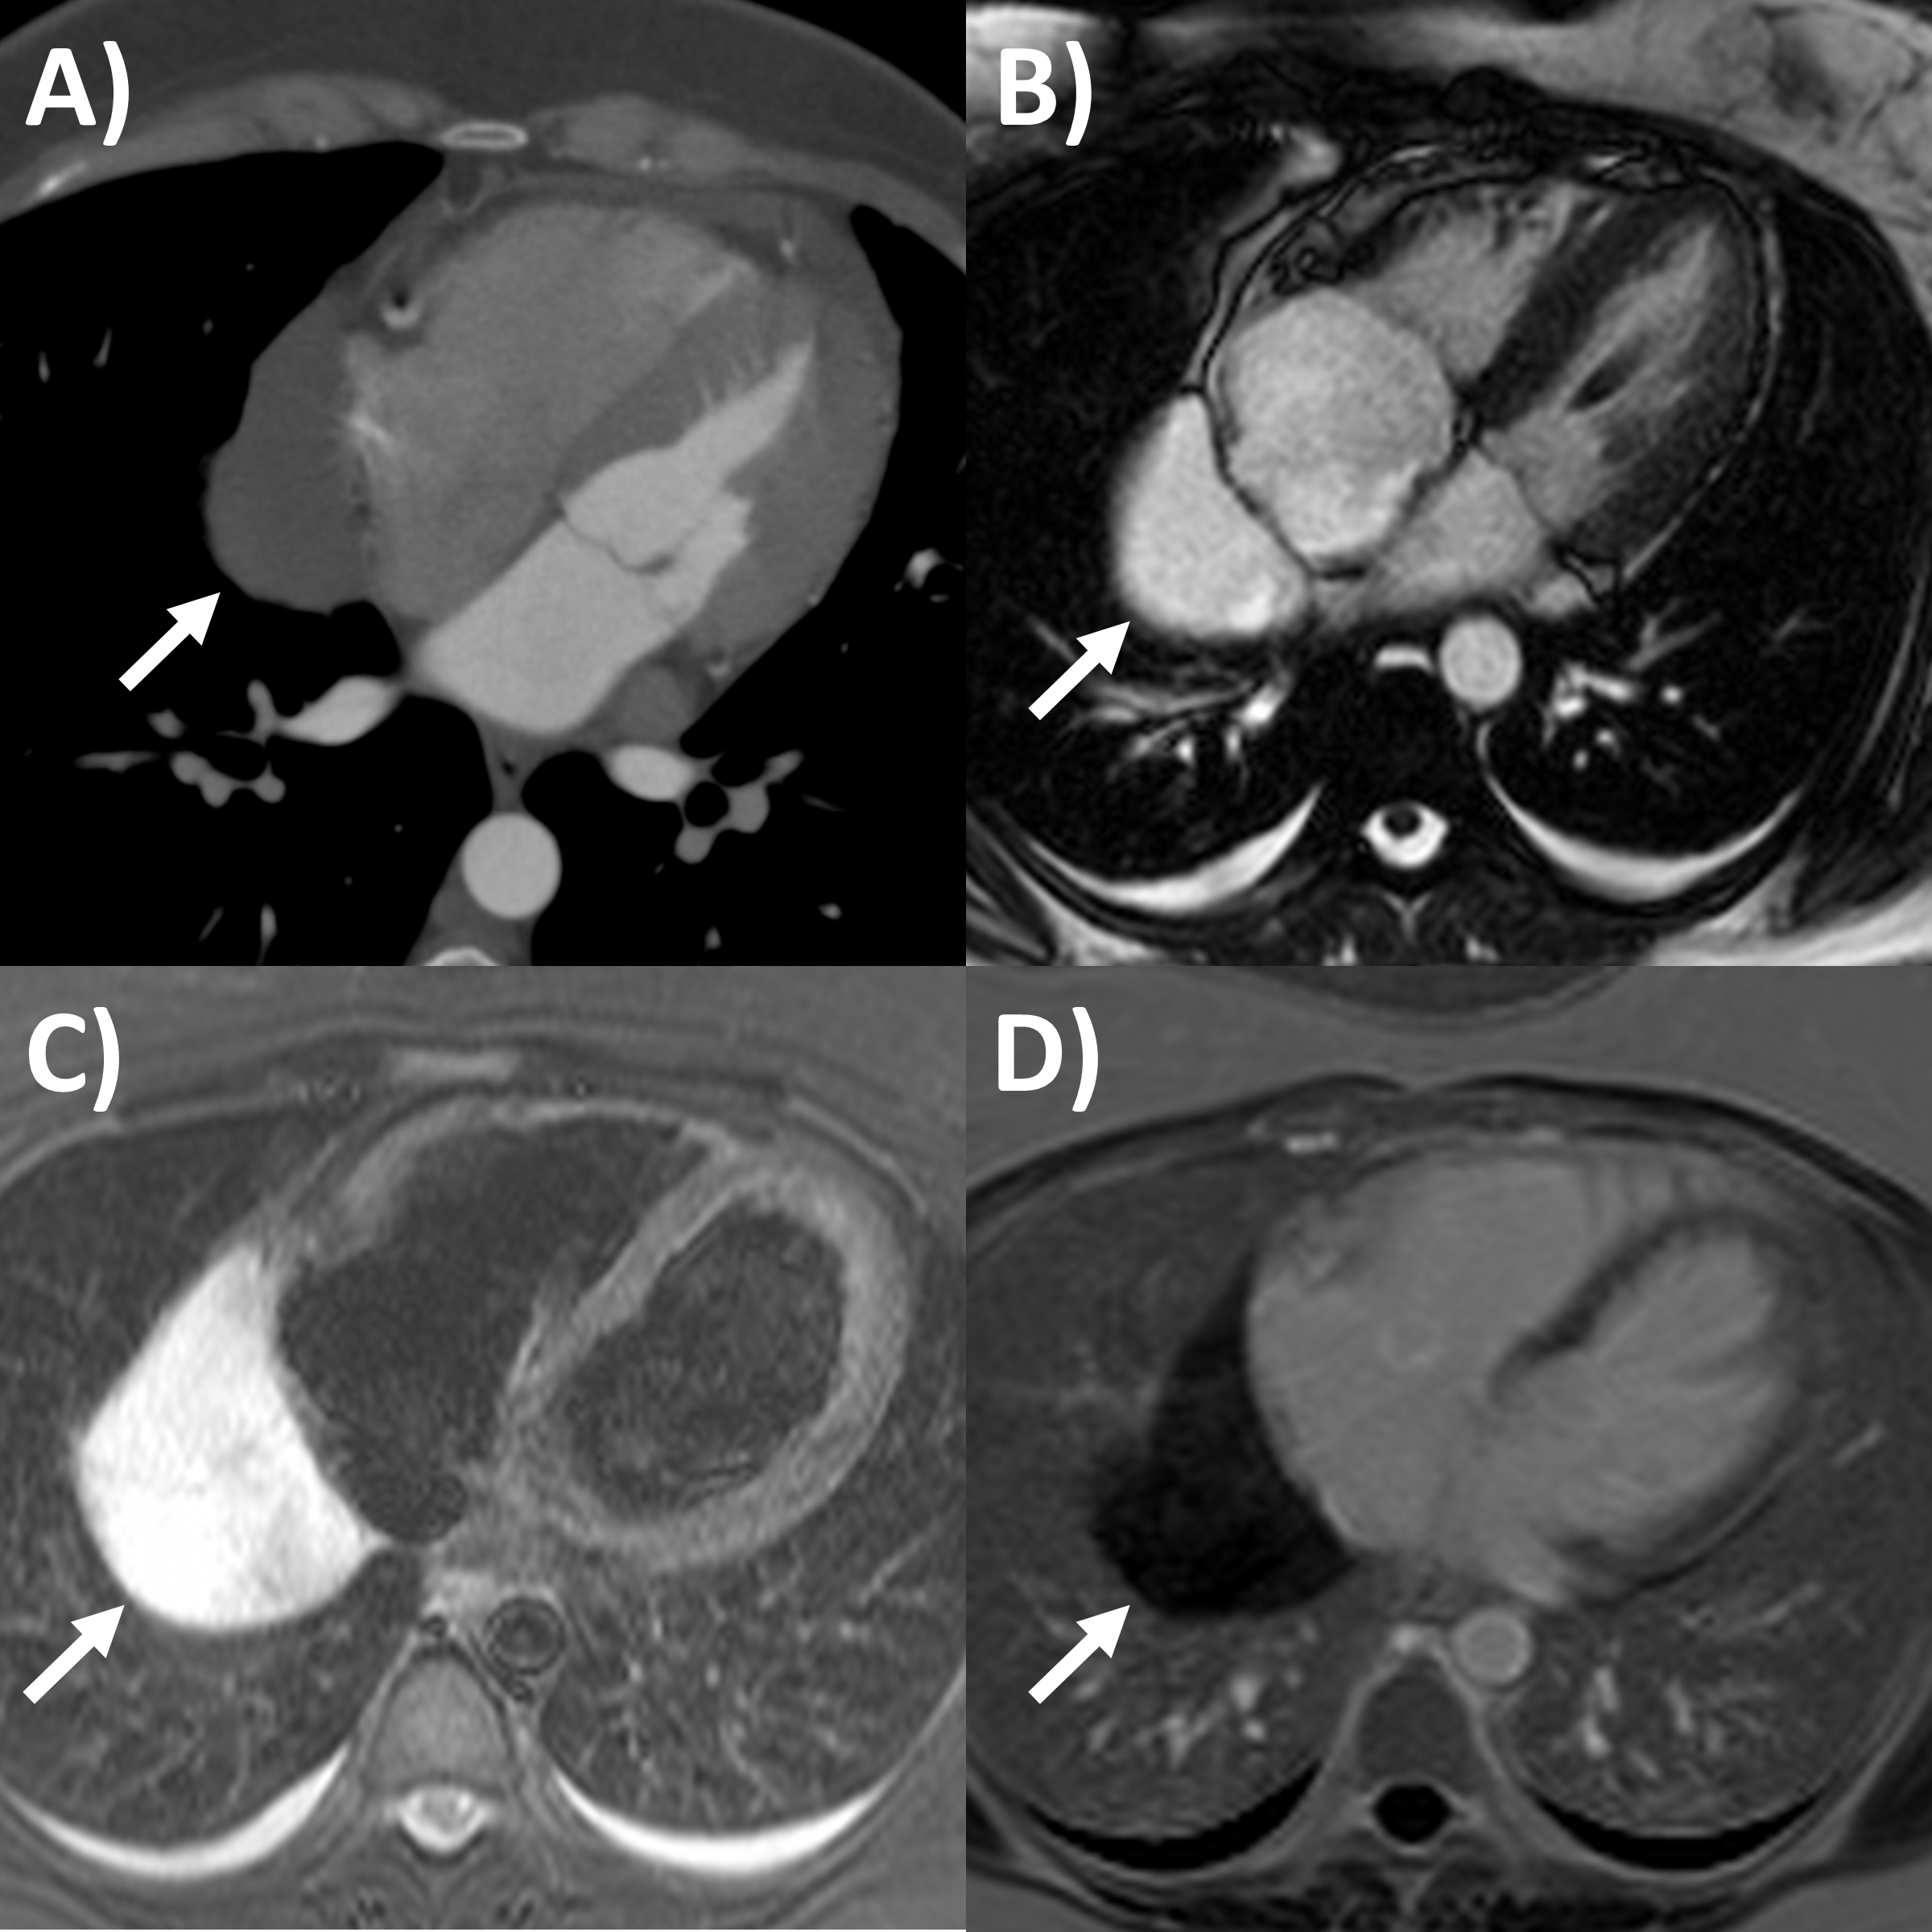

CT has greater ability for tissue characterization than echocardiography, and is able to assess the extent, local or distant spread of masses, lymph node involvement and many pericardial tumors have associated effusions that are hemorrhagic or exudative [31]. Hemangiomas appear heterogenous with contrast enhancement; lymphangiomas are heterogenous with low attenuation and septae; lipoma have low fat-level attenuation that is circumscribed, and sometimes can surround coronary arteries; teratomas usually have contain areas of calcification and fat; lymphoma are hypoattenuating with contrast enhancement; fibromas are homogeneous with no or minimal enhancement given lack of vascularity; sarcomas are broad-based masses which invade adjacent structures; and mesothelioma is seen as diffuse irregular pericardial thickening with effusion [31, 56]. Pericardial cysts are seen as a well-circumscribed homogeneous mass with thin wall on CT, with fluid density, unaffected by intravenous contrast (Fig. 4) [59, 60].

MRI’s main advantage amongst imaging modalities is its ability in tissue characterization, and this is no different when applied to pericardial masses. Depending on tumor extension, the pericardium or myocardium may show thickening, or pericardial effusions, the latter often exudative or hemorrhagic with high signal intensity on T1-weighted sequences [31]. On T1-weighted, T2-weighted and gadolinium enhanced sequences, many tumors have low, high and high signal intensities [14, 31, 61, 62, 63]. Hemangiomas generally appear heterogeneous on all sequences, while lipomas have high signal intensity on all sequences, however its signal can be uniquely suppressed on fat-saturation pulse sequences. Fibroma have low vascularity and therefore have low signal intensity on T2-weighted sequence and none to minimal enhancement on gadolinium enhanced sequences. Mesotheliomas appear homogeneous on T1-weighted but have heterogenenous elevated signal on T2-weighte and gadolinium enhanced sequences. Of note, some studies have suggested heterogenous gadolinium uptake to indicate areas of increased lesion nodularity, growth and/or necrosis [64]. Pericardial cysts also appear as a well-circumscribed homogeneous mass with thin wall on MRI, displaying hypointense signal on T1-weighted sequence unless there is an exudative or hemorrhagic component, with hyperintense signal on T2-weighted sequence and no signal on LGE sequence (Fig. 4) [31, 65]. Lastly, pericardial hematomas show hyperintense, heterogeneous and hypointense signal on T1 and T2 weighted sequences in the acute, subacute and chronic stages, and no signal on LGE sequences regardless of timeframe [31].

Congenital absence of the pericardium is a rare anomaly involving partial or complete absence of one or both sides of the pericardium, and complete left-sided absence being the most common [75, 76]. In a minority of patients there are associated other congenital heart diseases such as atrial septal defect and tricuspid atresia [77]. It is often an incidental finding in asymptomatic patients either on imaging (chest or cardiac) or during cardiothoracic surgery, although symptoms may include atypical chest pain, dyspnea, palpitations and dizziness. When echocardiography is performed, typical findings include unusual imaging windows, apparent right ventricular dilation, systolic paradoxical septal motion and excessive cardiac motion [75, 78]. CT and MRI provides direct visualization of its characteristic features in both axial and reconstructed views, such as leftward posterolateral displacement of the apex (levorotation – Fig. 6) and lung tissue interposition in unexpected locations (e.g., between base of heart and diaphragm, between aorta and pulmonay artery) [75]. High-risk imaging findings that may pre-dispose sudden death are left atrial appendage or other chamber herniation and strangulation, left ventricular hinge point or crease, and coronary artery compression or inducible ischemia on stress perfusion [76].

Fig. 6.Congenital absence of the pericardium on magnetic resonance imaging (axial slice steady state free precession bright blood sequence).